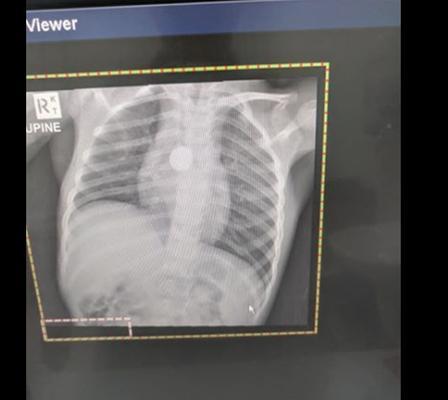

隔天兒科醫師進行檢查,並給卡麥克兒照X光,當時醫師讓媽媽把女兒身上的「項鍊」拿下來。媽媽卻說,「她根本沒戴項鍊啊」,這時醫師才驚覺大事不妙,X光看見的金屬物並不是項鍊,而是另有其物!

醫師當下就立刻為卡麥克兒安排手術,取出異物。經過了2個多小時的手術,醫師終於把卡在卡麥克兒食道深處的「鈕扣電池」給取出來。

這顆電池的邊已經被腐蝕,相信待在卡麥克兒的食道裡已有一段時間了。